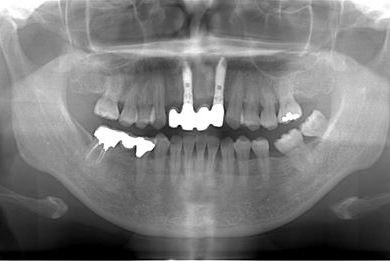

| 性別/年齢 | 女性 / 52歳 | ||||||||||||||||||||||||||||||||

| 主訴 | 歯周病で歯の位置がずれてしまった。 | ||||||||||||||||||||||||||||||||

| 治療内容 | インプラント2本(抜歯即日スピードインプラント)、メタルボンドセラミッククラウン4本 | ||||||||||||||||||||||||||||||||

| 治療期間 | 10ヶ月 |